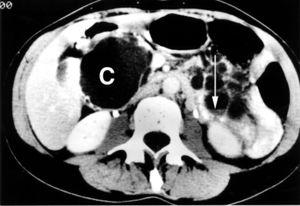

Large pancreatic cyst causing symptoms of early satiety.jpg

كيسة پنكرياس كبيرة عند الناتئ الشصي للپنكرياس.